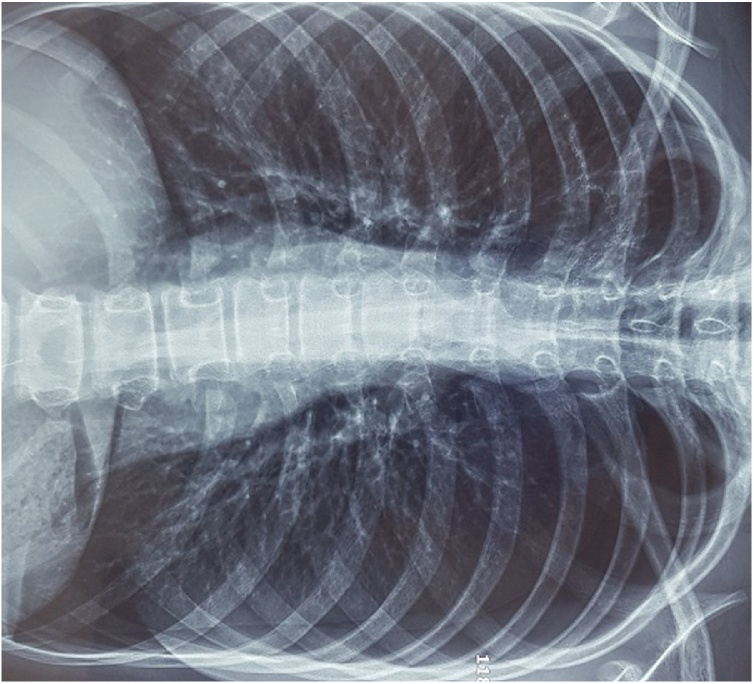

C: Chest CT scan shows bilateral apical subpleural blebs.

After 7 days in our ward with the encouragement of physiotherapy and medical therapy, the patient was clinically stable but still had a persistent air leak, a chest CT with IV contrast was obtained at this time and showed bilateral upper lobes apical segment bleb and non-expanded right lung (Fig. 1C).